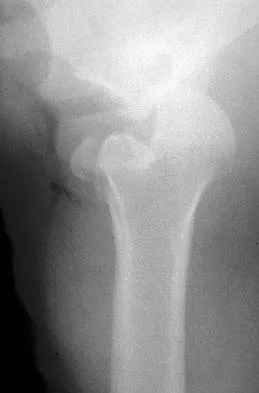

Figures 39a and 39b show the radiographs of an otherwise healthy 10-year-old boy who has had thigh pain and a limp for the past 9 months. Examination reveals that the left lower extremity is 1 cm shorter, with reduced flexion, abduction, and internal rotation on the left side. The patient is at the 50th percentile for height and the 90th percentile for weight. Serum studies will most likely show

Explanation

The patient has a slipped capital femoral epiphysis (SCFE) at a younger than average age (average age 13.5 years for boys and 12.0 years for girls); therefore, an etiology that is not idiopathic must be considered. Hypothyroidism can result in a SCFE, but these children typically fall into the category of less than the 10th percentile for height. SCFE may develop in children with a growth hormone deficiency who have undergone hormonal replacement. Osteodystrophy caused by chronic renal failure may result in a SCFE, but the bone quality is markedly osteopenic on radiographs and the children are chronically ill with both low height and weight percentiles. An elevated estrogen level results in physeal closure and is protective to physeal slippage. Therefore, this child will most likely have normal laboratory values. Loder RT, Hensinger RN: Slipped capital femoral epiphysis associated with renal failure osteodystrophy. J Pediatr Orthop 1997;17:205-211.